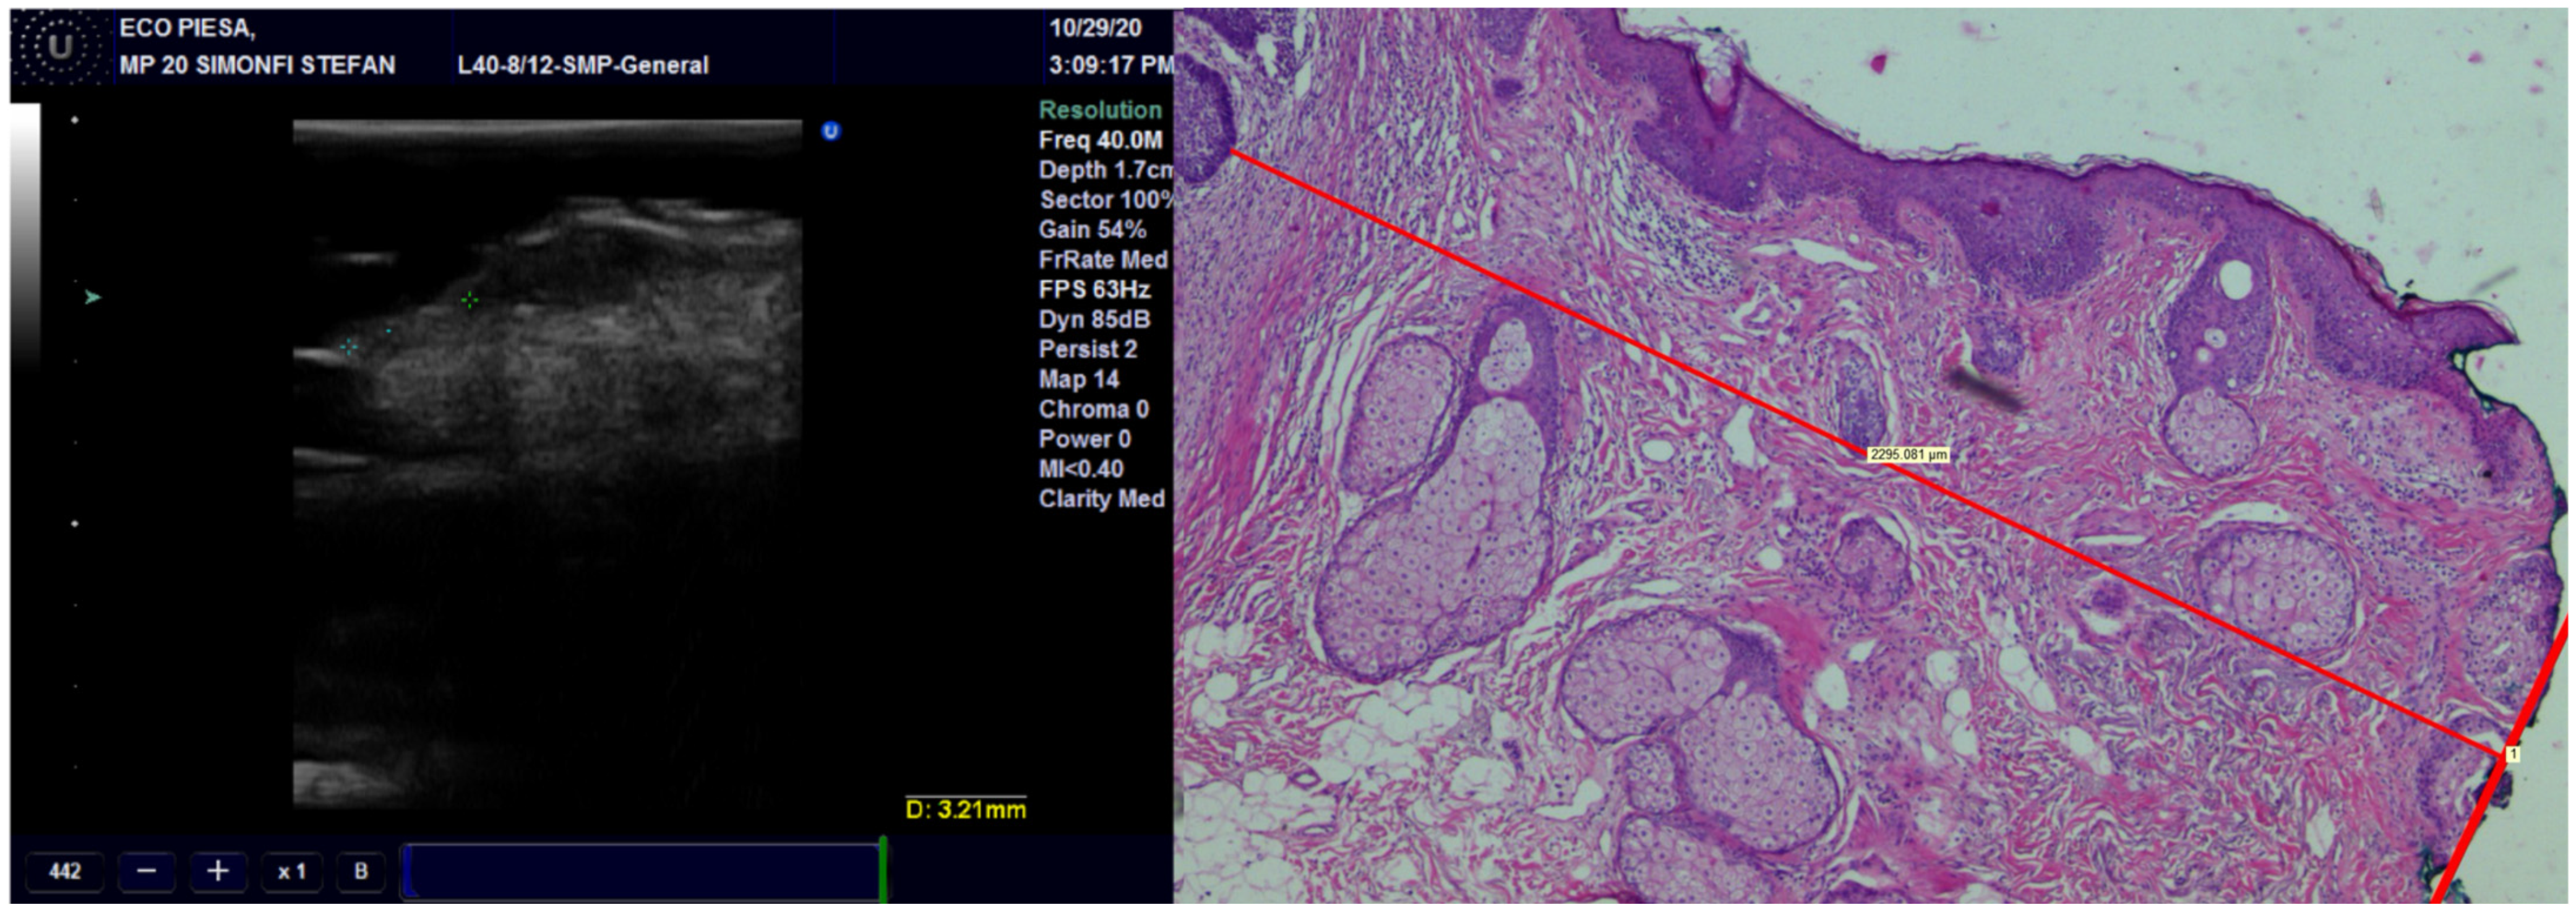

Concerning concordance between the histopathological and echographic measurements of tumor thickness, we found excellent agreement for all transducers, with the best ones being for the preoperative observations and the least favorable ones being the postoperative observations (Figure 3) (Table 2). Within any of the preoperative and postoperative observations, the 40 MHz transducer fared the best, followed by the 20 MHz transducer and finally by the 13 MHz transducer.

Figure 3.

The thickness of the tumor, measured on US with 20 MHz and 40 MHz transducers, compared with the pathological image of the tumor showing very high occurrence of US.